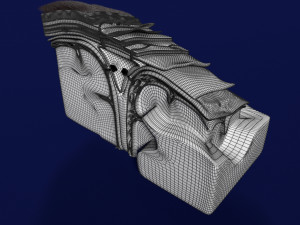

Brain with meninges scalp detailed labelled 3D 3D मॉडल

A blend model of brain along with its covering layers (meninges), skull bone and scalp labelled in detail and anatomically precise. The parts depicted are white, gray, pia, arachnoid, dura, bone, skin, fat, aponeurosis, periosteum, falx cerebri and more.

The material is high resolution image textures and normal maps based on non overlapping UVs. The texture and normal maps are packed with the blend file itself.